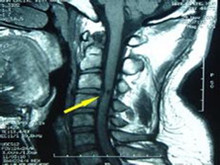

急性化膿性脊髓炎極為罕見(jiàn),是由急性化膿性感染后引起急性脊髓炎癥。本病常并發(fā)脊髓內(nèi)膿腫。急性化膿性脊髓炎多累及胸段脊髓,最初有畏寒及發(fā)燒,出現(xiàn)疼痛,迅速發(fā)展成截癱。

• 應(yīng)該做哪些檢查項(xiàng)目呢?血常規(guī)、腦脊液檢測(cè)、脊髓造影(椎管造影)、脊柱MRI、X線平片